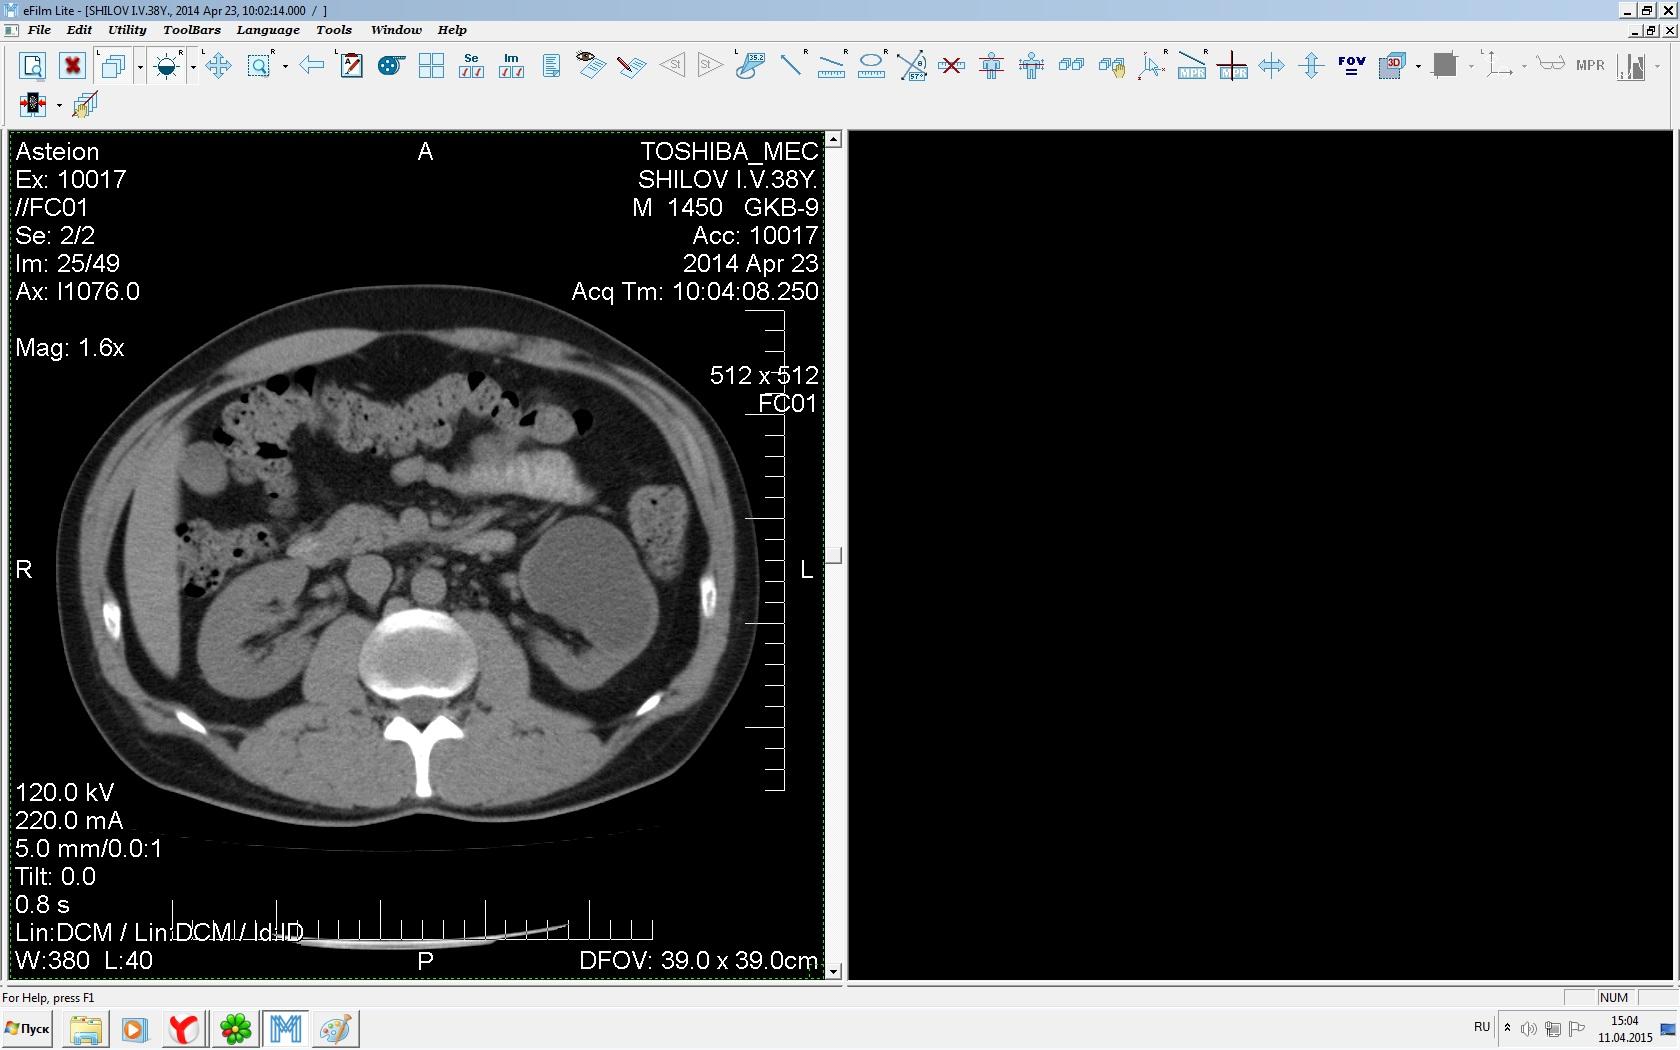

Здравствуйте. У меня киста левой почки. Из заключения: левая почка увеличена, деформирована за счёт наличия в среднем сегменте округлого жидкостного +6, +15 HU образования 66х53 мм, деформирует, поддавливает чаше-лоханочную систему. Сосудистые ножки структурные. В урологии мне сперва предложили лапароскопию, когда я лёг на операцию - изменили на полостную в связи со сложностью. Потом сказали что шансов вырезать кисту без почки практически нет. Даже если кисту удалить чудесным способом, то почка всё равно сложится и не будет работать. В итоге операцию отменили. Скажите, пожалуйста, есть ли современный метод удалить кисту и сохранить почку в моём случае? Томография почки в приложениях. Заранее благодарю.

Эту кисту можно просто пропунктировать, аспирировать и склерозировать - под местной анестезией. Ничего сверхестетственного не определяется по данным КТ. Можете написать мне на почту. aristova-tatyana@mail.ru